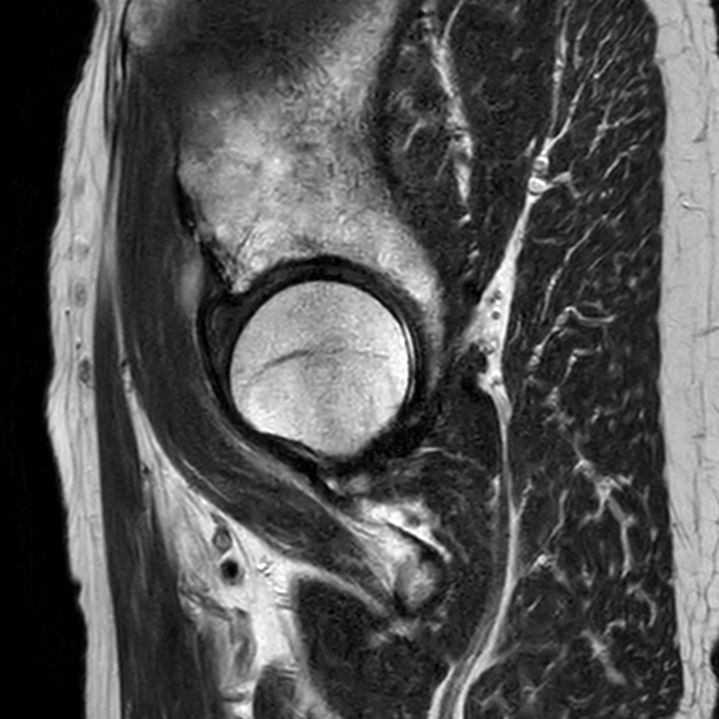

Sagittal T2w TSESmartSpeed Resolution

-